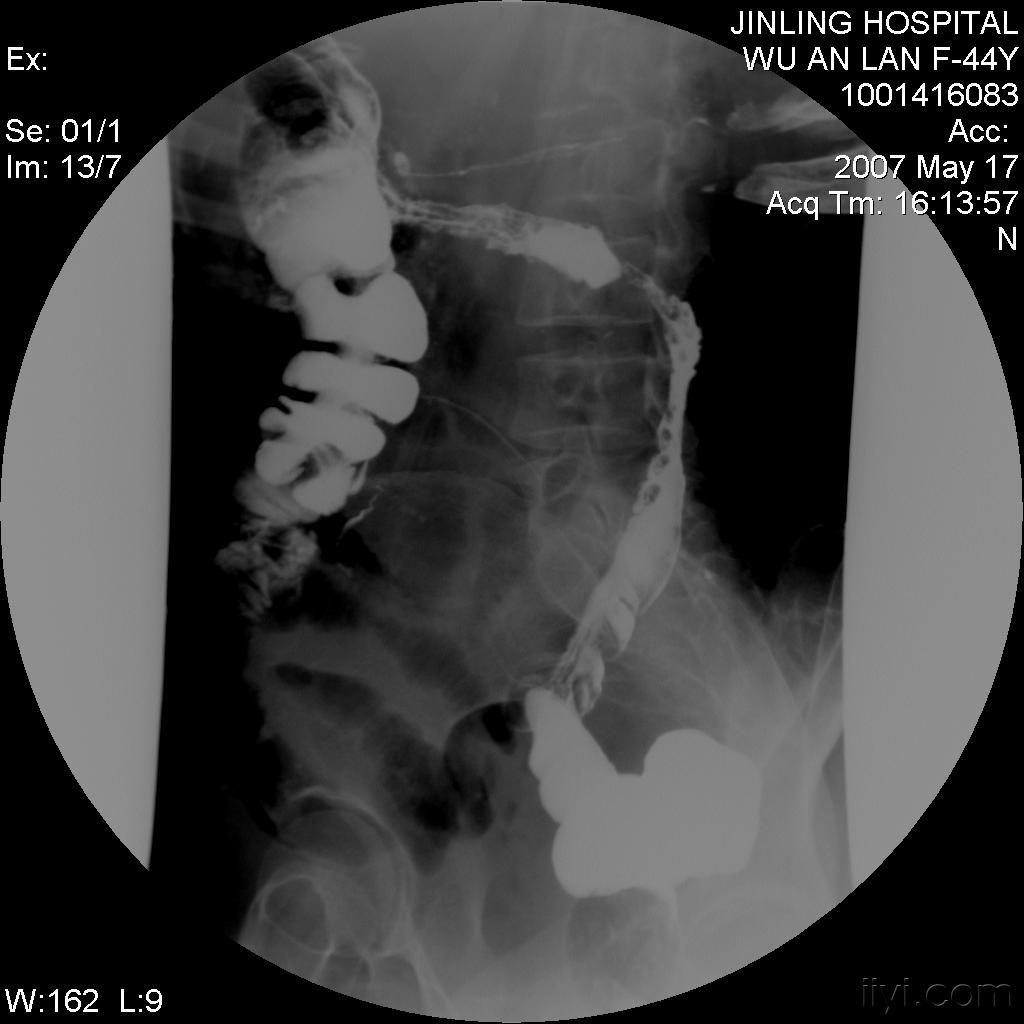

直到有一天,一位内科医生建议我进行一系列深入的检查。通过内镜检查和影像学检查,他们发现了肠道的异常炎症和穿透性病变,这些特征与克罗恩病的诊断标准高度吻合。那一刻,我的心情复杂难言,既有终于找到病因的释然,也有对未来治疗道路的担忧。

克罗恩病的诊断并非易事,它需要医生通过详细的临床症状观察、实验室检查和影像学检查来综合判断。对于我来说,这个过程是漫长而艰辛的,但也是我与。